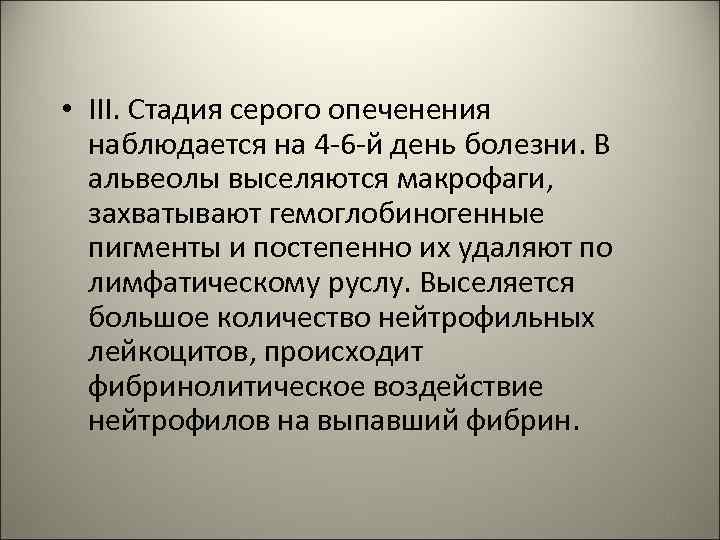

1225 – стадия красного опеченения легкого 50

• III. Стадия серого опеченения наблюдается на 4 -6 -й день болезни. В альвеолы выселяются макрофаги, захватывают гемоглобиногенные пигменты и постепенно их удаляют по лимфатическому руслу. Выселяется большое количество нейтрофильных лейкоцитов, происходит фибринолитическое воздействие нейтрофилов на выпавший фибрин. 51

1009 – стадия серого опеченения легкого 52

• Цвет легкого меняется - легкое становится серым. Пораженная доля легкого увеличивается в размере, плотная, тяжелая, на плевре значительные фибринозные наложения. Лимфатические узлы корня легкого увеличены. 53